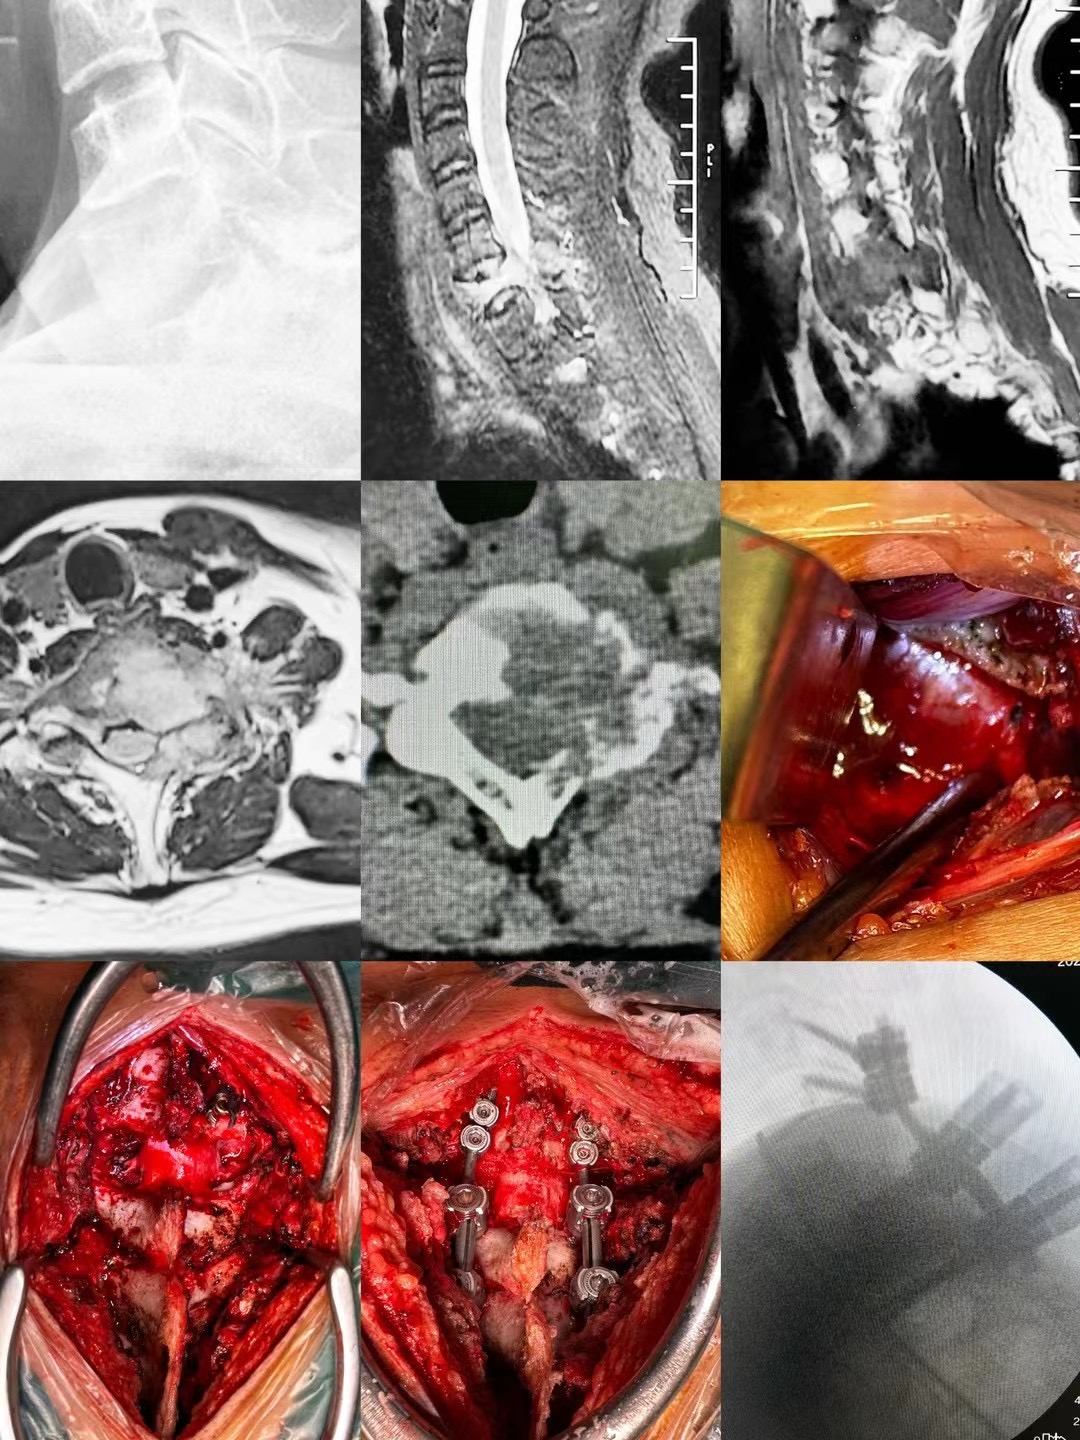

近日,骨二科臧全金副主任医师团队成功完成一例复杂脊柱手术。患者为颅底凹陷症合并脊柱侧凸,已经在西安多家医院门诊就诊,并在某知名三家医院住院治疗,但均未获得良好诊治。后来在北医三院主任医师推荐下来到臧全金副主任医师处治疗。接诊后,臧全金发现患者为严重的颅底凹陷症合并脊柱侧弯,实属罕见,治疗难度大,风险高。但正是这样的病例激起了他的兴趣,术前其带领的治疗团队详细研读了患者的影像资料,制定了详尽的手术方案,于近日一期完成了颅底凹陷症的解剖复位和脊柱侧凸截骨矫形术,术后患者恢复良好,无任何神经并发症。颅底凹陷症合并寰枢椎脱位、脊柱侧凸两种疾病任何任何一种在脊柱外科都属于高难度复杂手术,在脊柱外科领域都属于珠穆朗玛峰般的存在,西北地区只有少数几家三甲医院开展此类疾病的手术治疗,而能够主刀完成这种手术的医生少之又少。看到孩子顺利完成手术,患者家属感到特别高兴,再三感谢臧全金副主任医师团队高超的手术技艺以及过人的胆识,为自己的孩子解决了困扰多年的疾病。

像这样的高难度颈椎手术,臧全金副主任医师带领曹凯博士、郭帅博士的团队近期已完成了多例,均取得了良好的手术效果。一例外省的颈椎肿瘤患者,慕名从省外来到骨二科,在臧全金副主任医师团队的精心治疗下,一期前后路切除肿瘤,完成颈椎重建,术后神经功能得到恢复。多例颈椎后纵韧带骨化患者,椎管内占位达到椎管前后径的70-80%,脊髓被压得只剩下一条线,臧全金带领的团队精雕细琢,为患者完成减压,术后患者从蹒跚行走到灵活小跑;颈椎间盘突出压迫脊髓瘫痪患者在臧全金团队的治疗下从卧床到下地行走…………为了解决患者的病痛,臧全金急患者之所急,近一周从家中赶往医院为两次颈椎脱位脊髓损伤患者行急诊手术,第一时间挽救患者脊髓功能。很多病例不一例数。